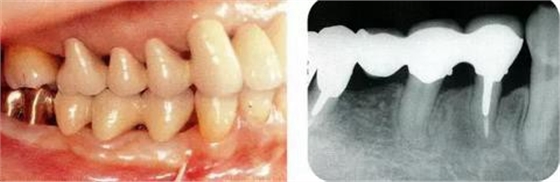

圖18-1(左),2 (右)▲初診時(shí)口腔內(nèi)照片和X線片,右下4近中有較深的1壁性骨缺損,右下45有根接近。如果在這個(gè)情況下進(jìn)行骨外科處理,需要犧牲較多的右下3遠(yuǎn)中的牙槽骨。也會(huì)造成周圍骨形成較大的臺(tái)階。

圖18-3▲佩戴臨時(shí)冠后,右下4應(yīng)用正畸邊挺出邊向近中移動(dòng)。結(jié)果改善根接近的問題,右下4近中所存在的較深的骨缺損向右下5和右下4較淺的骨缺損擴(kuò)散。在這個(gè)情況下,應(yīng)用牙周外科的處理就會(huì)比較合適。